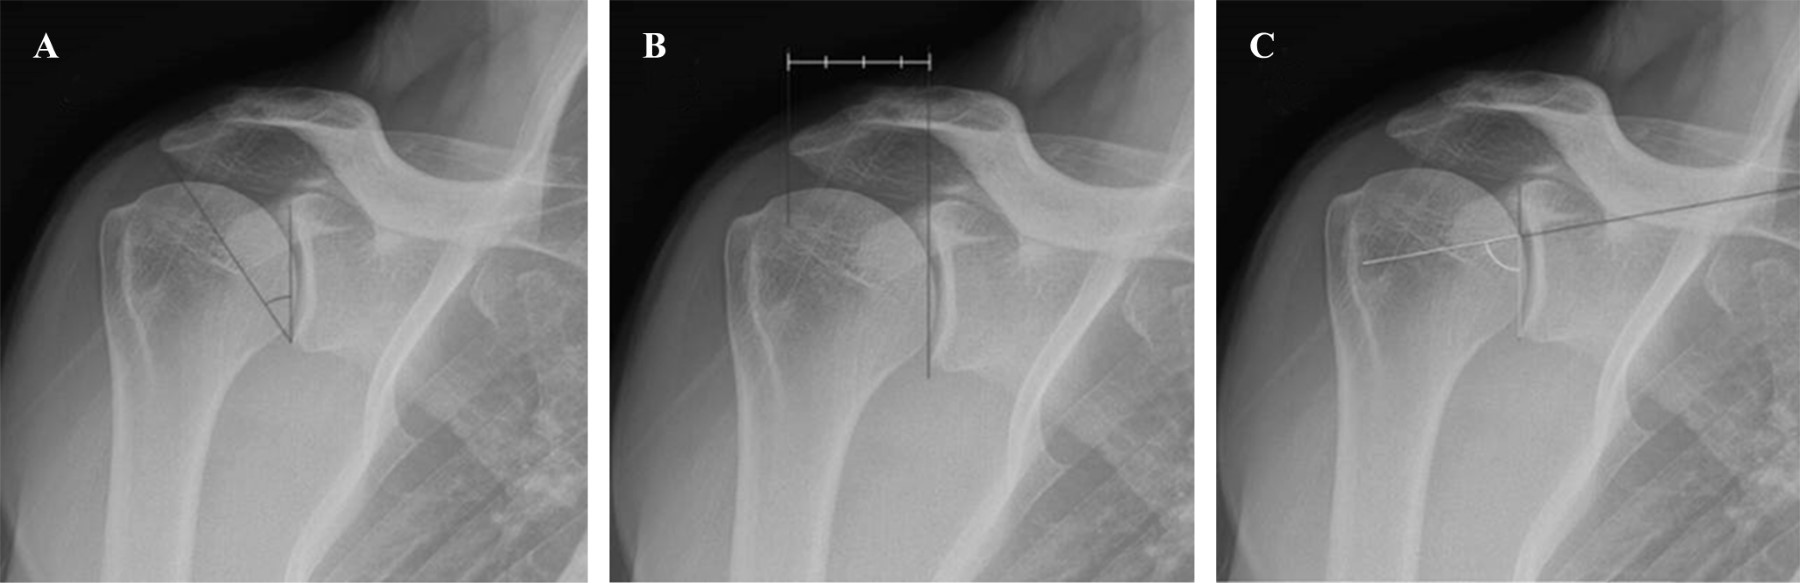

Moor, en 2013, desarrolló el concepto de ángulo crítico del hombro (ACH), un ángulo que se forma entre una línea que va del borde inferior al borde superior de la glenoides (plano de la fosa glenoidea) y una línea que va del borde inferior de la glenoides al borde lateral del acromion; medido esto en una radiografía anteroposterior verdadera de hombro, también conocida como proyección de Grashey.10,11

El ACH toma en cuenta indirectamente dos parámetros: la lateralidad acromial y la inclinación glenoidea, el aumento en la primera o una disminución en la segunda será considerado un factor de riesgo para el desarrollo de LMR.15 La inclinación glenoidea o ángulo beta (formado entre una línea que pasa por el borde superior e inferior de la glena y una que pasa por el suelo de la fosa supraespinosa) es el grado en que la glenoides se inclina hacia arriba en relación con la escápula. Un aumento de esta inclinación (disminución del ángulo), causa una traslación superior del húmero. La lateralidad acromial (distancia desde la glena hasta la parte más lateral del acromion) es la extensión lateral del acromion respecto a la glena y su aumento causa un mayor brazo de palanca sobre el deltoides (Figura 1).16